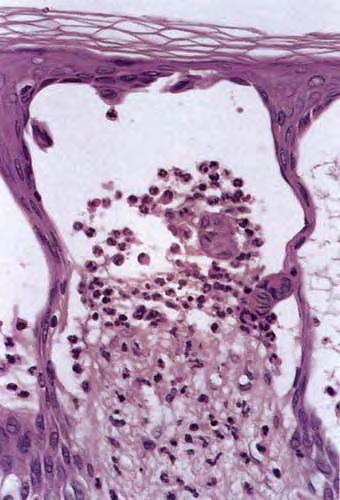

Histopathology

. The typical histologic features are best observed in erythematous skin adjacent to early blisters. In these zones, neutrophils accumulate at the tips of dermal papillae. With an increase in size to microabscesses, a significant admixture of eosinophils may be noted. As microabscesses form, a separation develops between the tips of the dermal papillae and the overlying epidermis; thus, the early blisters are multiloculated . The presence of fibrin in the papillae may give them a bluish appearance. Within 1 to 2 days, the rete ridges lose their attachment to the dermis, and the blisters then become unilocular  and clinically apparent. At this time, the characteristic papillary microabscesses may be observed at the blister periphery. For this reason, the inclusion of perivesicular skin in the biopsy specimen is of

utmost value. The papillary dermis beneath the papillae may have a relatively intense inflammatory infiltrate of neutrophils and some eosinophils. Many neutrophils may exhibit leukocytoclasis. Subjacent to this, a perivascular infiltrate composed of lymphocytes, neutrophils, and eosinophils may be apparent. the diagnostic finding of papillary microabscesses may not be present in all patients. Apoptotic keratinocytes may be noted above the papillary microabscesses.